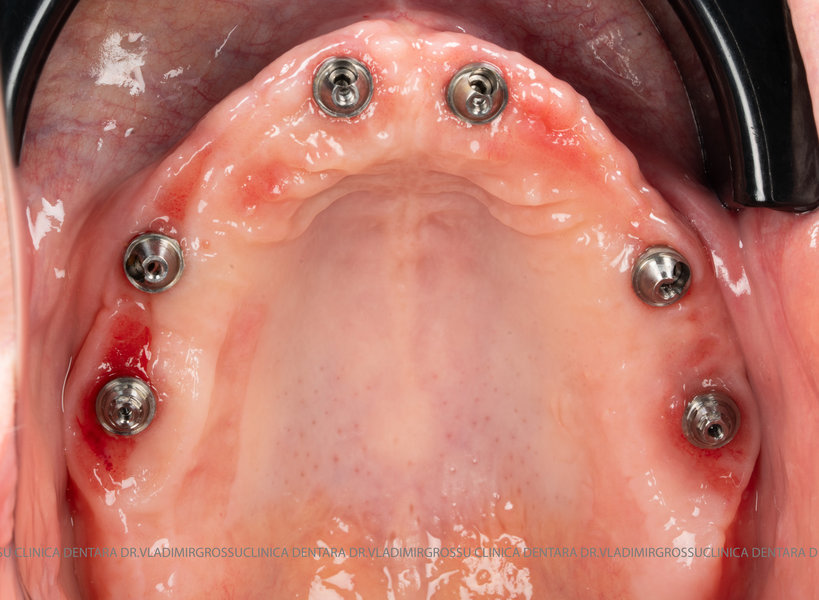

Această metodă este indicată pacienților cu edentație totală sau cu lipsuri dentare multiple, când dinții rămași nu mai pot susține o proteză fixă eficientă. Procedura se desfășoară în două etape:

- Prima etapă constă în inserarea implanturilor și fixarea unei proteze provizorii, realizate de obicei din masă plastică frezată, ce este montată în a doua sau a treia zi postoperator. Suturile sunt îndepărtate după 5-7 zile.

- A doua etapă are loc la aproximativ 6 luni după intervenție, când se realizează proteza definitivă, care este fixată pe implanturi prin intermediul unor piese numite multiunit-uri. Această etapă presupune lucrul la nivelul multiunit-urilor, nu direct pe implanturi, reducând astfel riscul de complicații.

- Șase multiunit-uri, drepte sau angulate, în funcție de necesitățile protetice;

- Șase capete de confort;